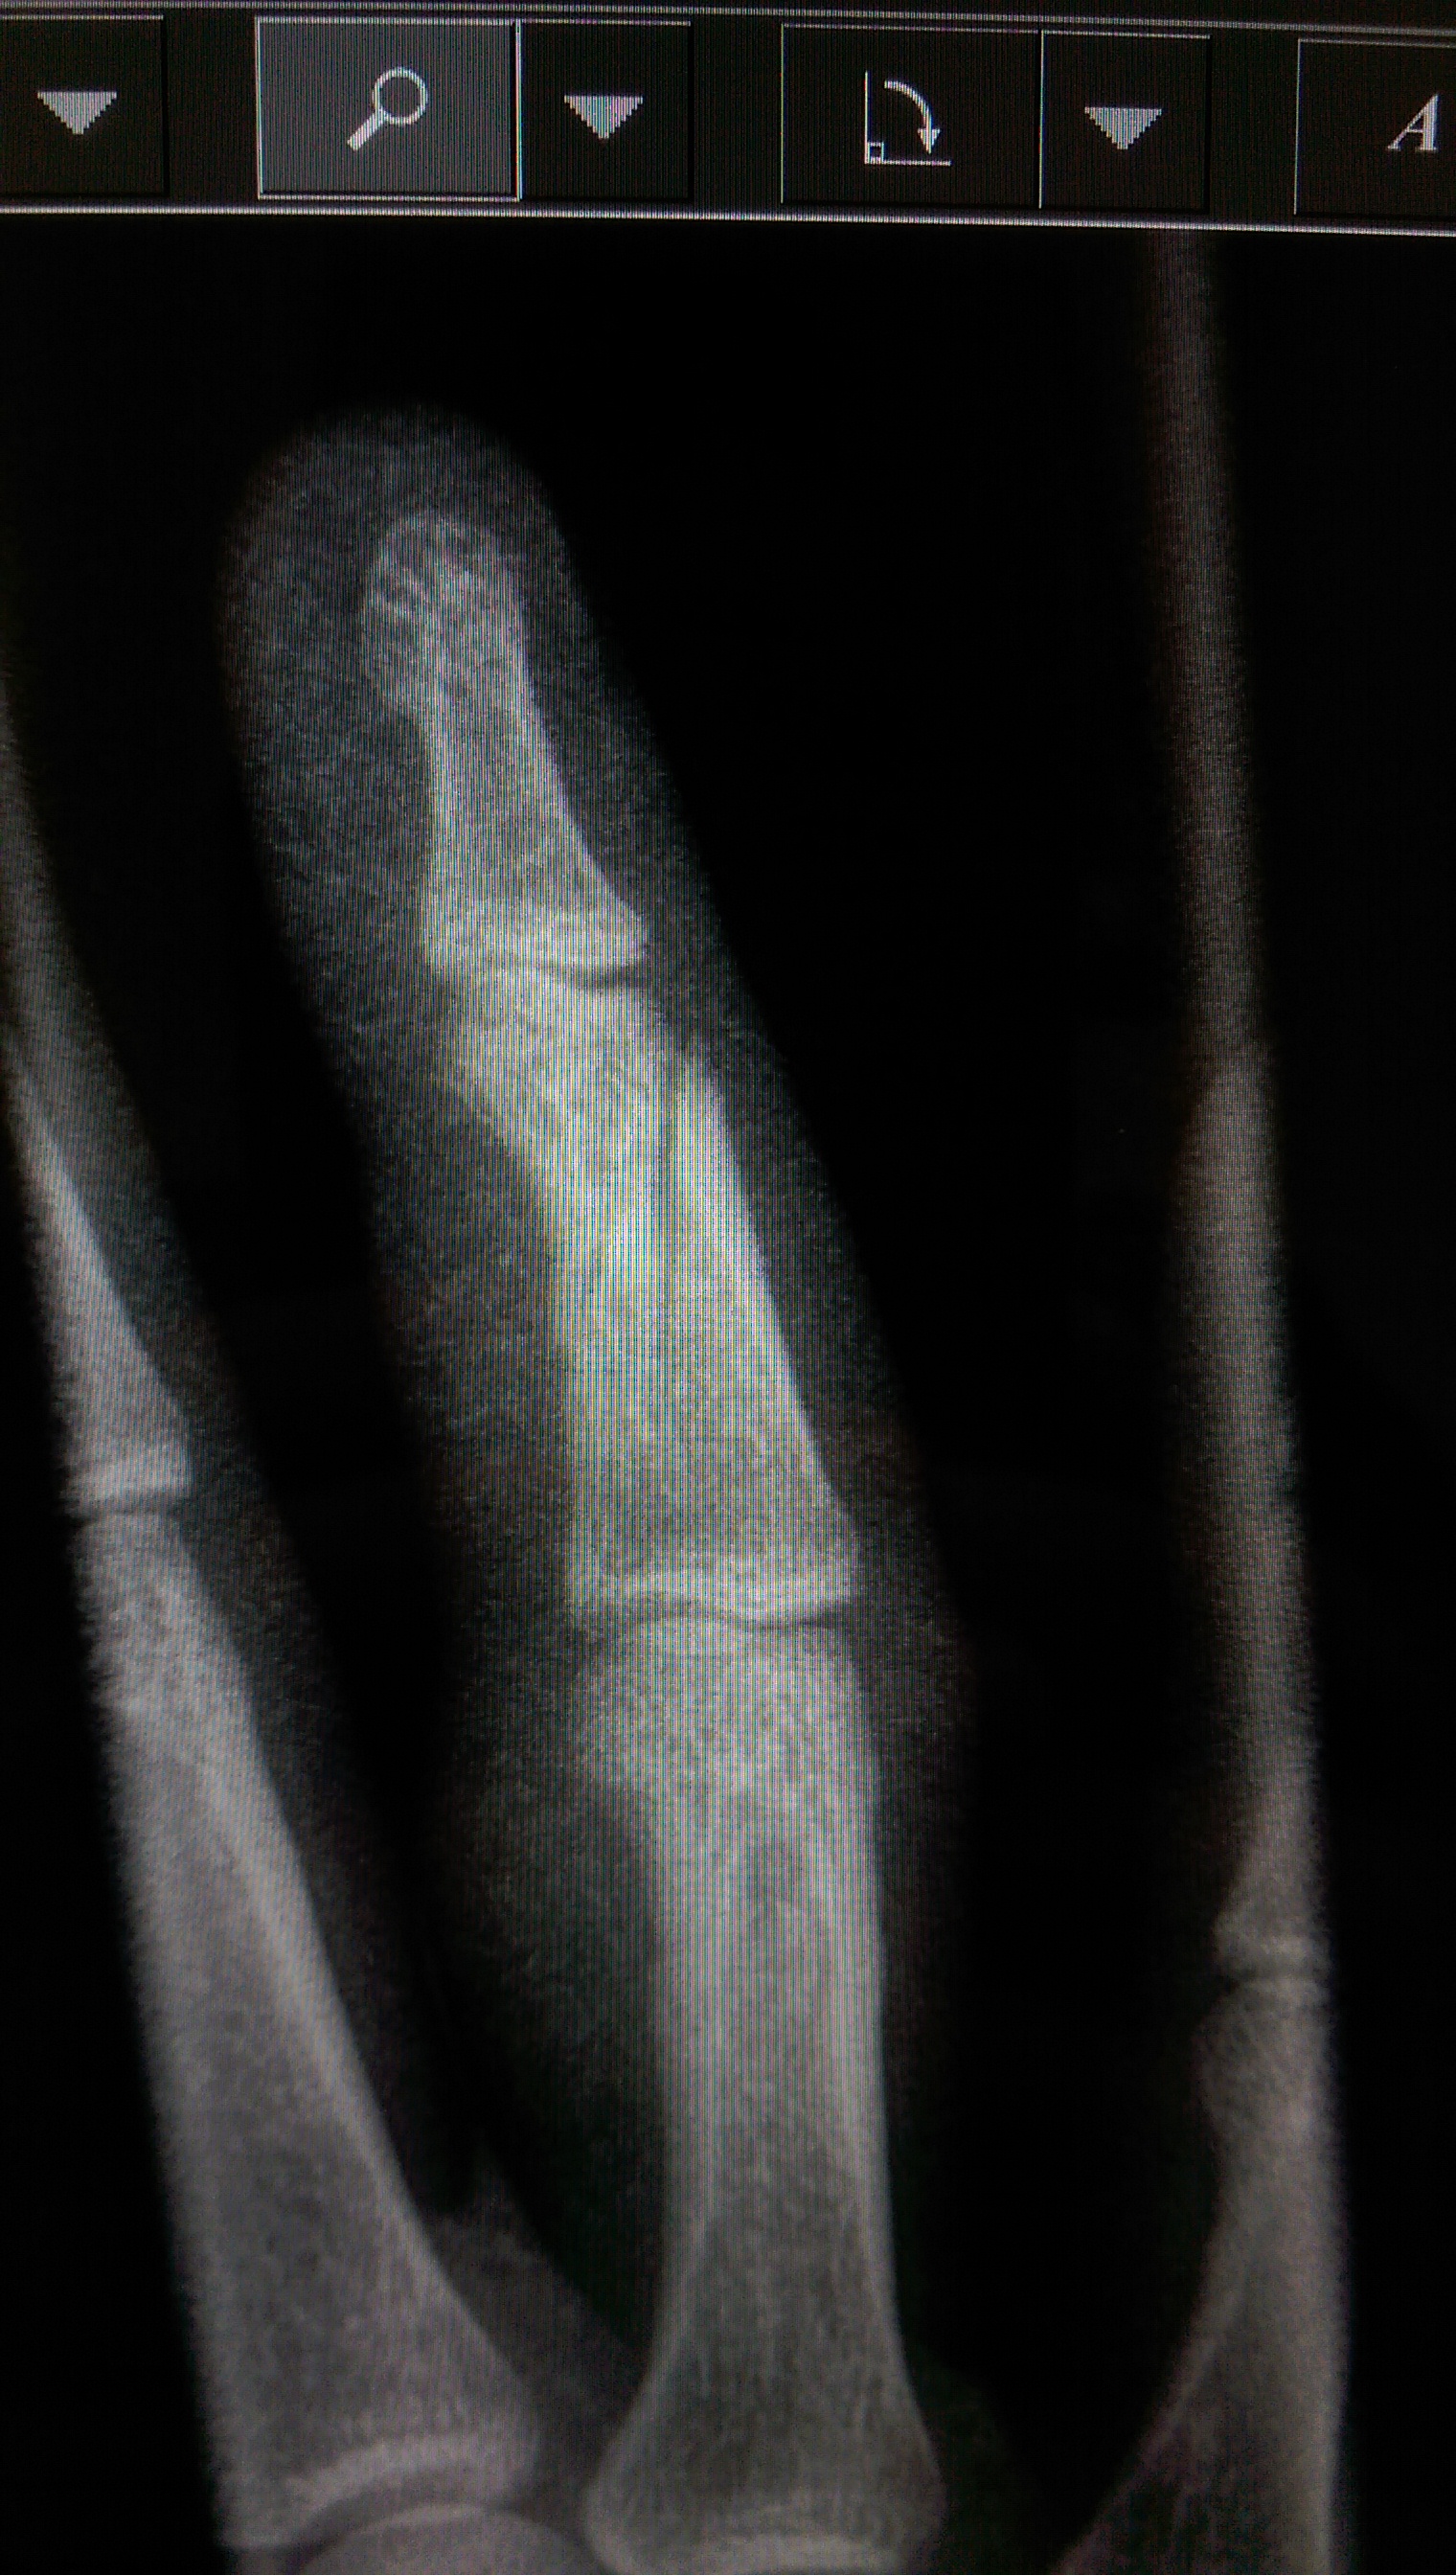

Behold, an alternative view: